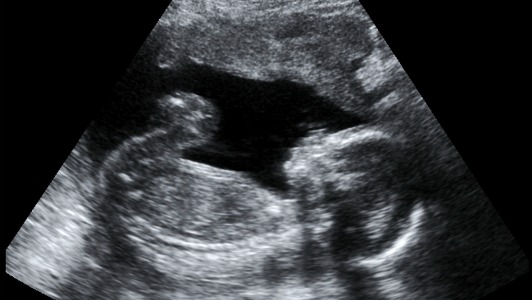

Des chercheurs de l’Université de Cambridge ont découvert le processus moléculaire qui lie une malnutrition in utero à une augmentation du risque de diabète de type 2 pour le futur enfant, même en l’absence d’obésité à l’âge adulte.